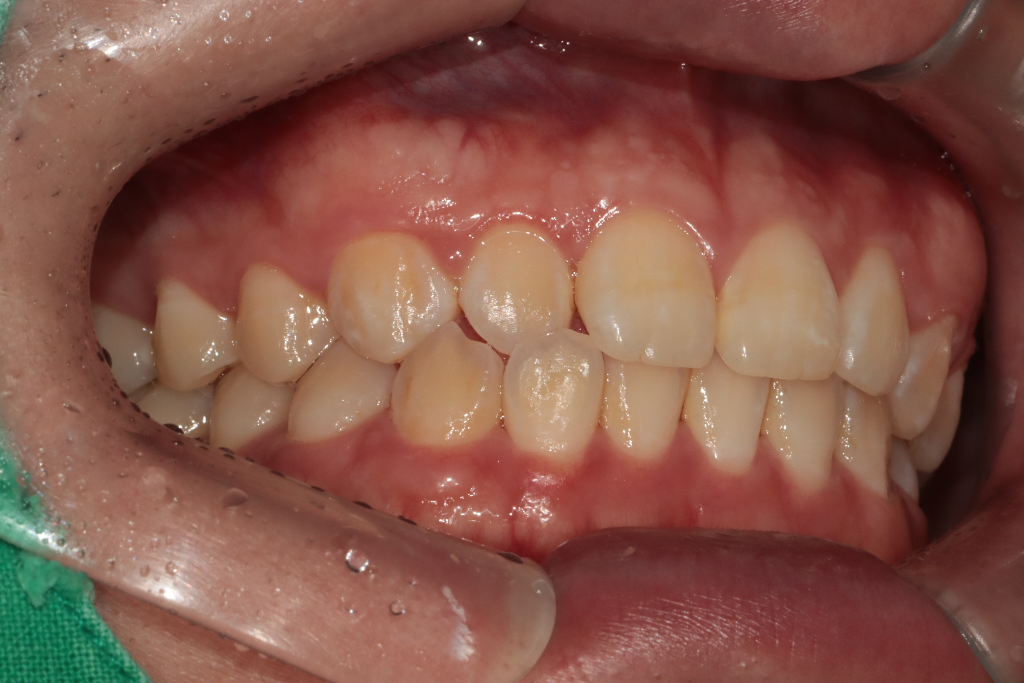

당연히 치아를 꽉 깨물고 있으면 불편감이 잇습니다. 치과 악습관중에 이꽉깨물기 이갈이등이 있습니다. 앞니 교합이 긴밀하신거 같긴합니ㅏㄷ.